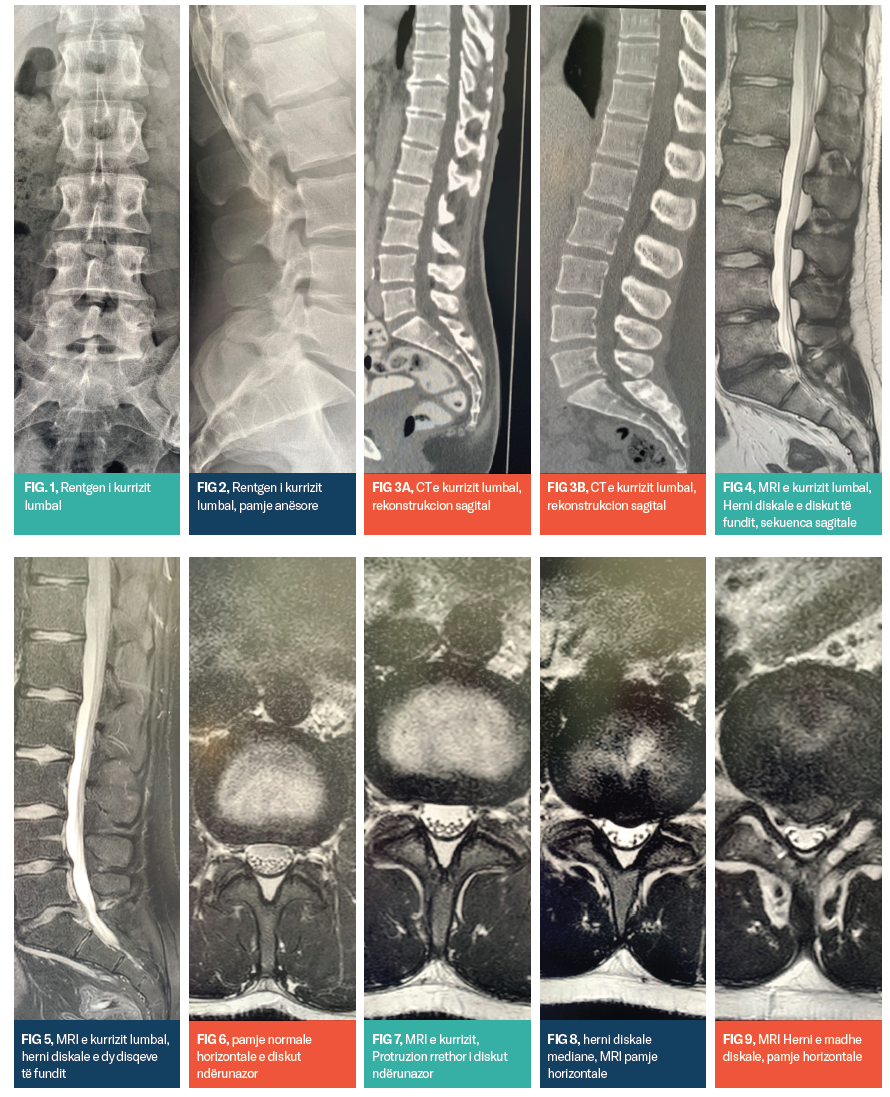

Zakonisht metoda e parë për ekzaminim të pacientëve me dhimbje të kurrizit është Rentgeni (shiko Fig 1 dhe 2).

Me anë të një fotografimi të Rentgenit do të marrim informacione shumë të rëndësishme për gjendjen e kurrizit, strukturën, gjendjen e unazave, dëmtimet eventuale, ndryshimet degjenerative, frakturat, lezionet e ndryshme të eshtrave, apo raportin e unazave në mes veti në strukturën e përgjithshme të kurrizit.

Ekzaminimet me tomografi të kompjuterizuar (CT): Në rastet kur pas një fotografimi me Rentgen mbesin çështje të paqarta apo të padefinuara apo kuadri klinik na sugjeron se kemi një gjendje ende të paqartë, atëherë metodë e ardhshme ekzaminuese është tomografia e kompjuterizuar (CT-ja), shiko Fig 3a dhe 3b. Me ndihmën e këtij ekzaminimi do të marrim informacione të tjera me rëndësi diagnostike: sqarimi i mëtejmë i lezioneve të vërejtura në Rentgen, prezantimi tredimensional i kurrizit dhe i lezioneve, prezantimi i disqeve ndërunazore (që me Rentgen nuk është i mundur), gjendjen e kanalit të boshtit kurrizor, gjendjen e nyjave ndërunazore dhe raportet e kurrizit me organet tjera.

Ekzaminimet me MRI (imazheri me Rezonancë magnetike): MRI është metoda më e mirë dhe më e saktë për diagnostikim imazherik tek njeriu. Në krahasim me CT-në dhe të gjitha metodat tjera, kemi një metodë në dispozicion, me një rezolucion shumë të lartë të diferencimit të indeve të ndryshme, që nga indet e buta deri te eshtrat: përcaktimi i saktë i diagnozës tek rastet e patologjisë së disqeve ndërunazore me diferencim dhe saktësim të lartë të llojit të patologjisë, shkallës së ngushtimit të kanalit të boshtit kurrizor, raportit të diskut të ndryshuar ndërunazor me strukturat përreth, sidomos me rrënjët e nervave dhe palcën e kurrizit. Diagnostikimi i saktë i ndryshimeve inflamatore, tumorale, sistemike apo post-traumatike. MRI sot është metodë e artë e diagnostikës imazherike. Është me rëndësi të potencohet çdoherë se MRI bazohet në parimet e rezonancës magnetike dhe se nuk ka rrezatim!

Prezantimi i kurrizit me MRI tek diagnostika e disqeve ndërunazore parimisht mund të ketë këto stade:

1.- Pamja normale e disqeve ndërunazore (shiko Fig 6). Në pamjet horizontale disku nderunazor nuk i tejkalon përmasat e korpusit unazor dhe kanali i boshtit kurrizor prezantohet me gjerësi normale ndërsa strukturat e kanalit të boshtit kurrizor, si palca kurrizore, qeska durale me fijet nervore si dhe radixet e nervave prezantohen të lira dhe të rregullta.

2.- Protruzioni i diskut nderunazor (shiko Fig 7): Me protruzion të diskut ndëruanzor kuptojmë zgjerim dorzal të diskut i cili ka forma të ndryshme, por zakonisht në formë koncentrike rrethore apo ovale zgjerohet në kanalin e boshtit kurrizor dhe ne hapësirat neuroforaminale.

3.- Hernia diskale e diskut ndërunazor /shiko Fig 8 dhe 9): Hernia diskale është forma më e komplikuar e zgjerimit të diskut, që si pasojë e çarjes në unazën kërcore prezantohet si një zgjerim ekscentrik, e ngushton në masë të theksuar kanalin e boshtit kurrizor dhe hapësirat neuroforaminale me tangim, impresion apo kompresion të qeskës durale dhe rrënjëve të nervave, varësisht nga madhësia e hernisë. Hernitë diskale për nga madhësia mund të jenë të vogla dhe të mëdha. Për nga manifestimi mund të jenë subligamentare, transligamentare dhe me migrim / sekuestrim te pjesëve te herniuara të diskut.